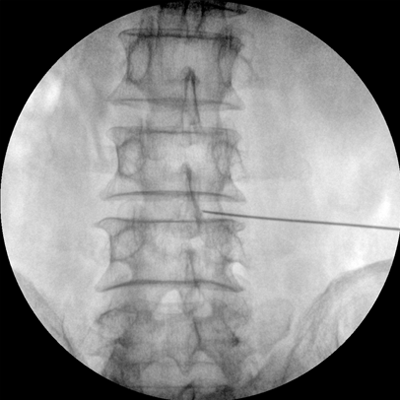

四維電動(dòng)運(yùn)動(dòng)控制,平滑定位,使得復(fù)雜角度快速實(shí)現(xiàn)。

專業(yè)的圖像處理系統(tǒng),為您提供高分辨率、高灰階圖像。